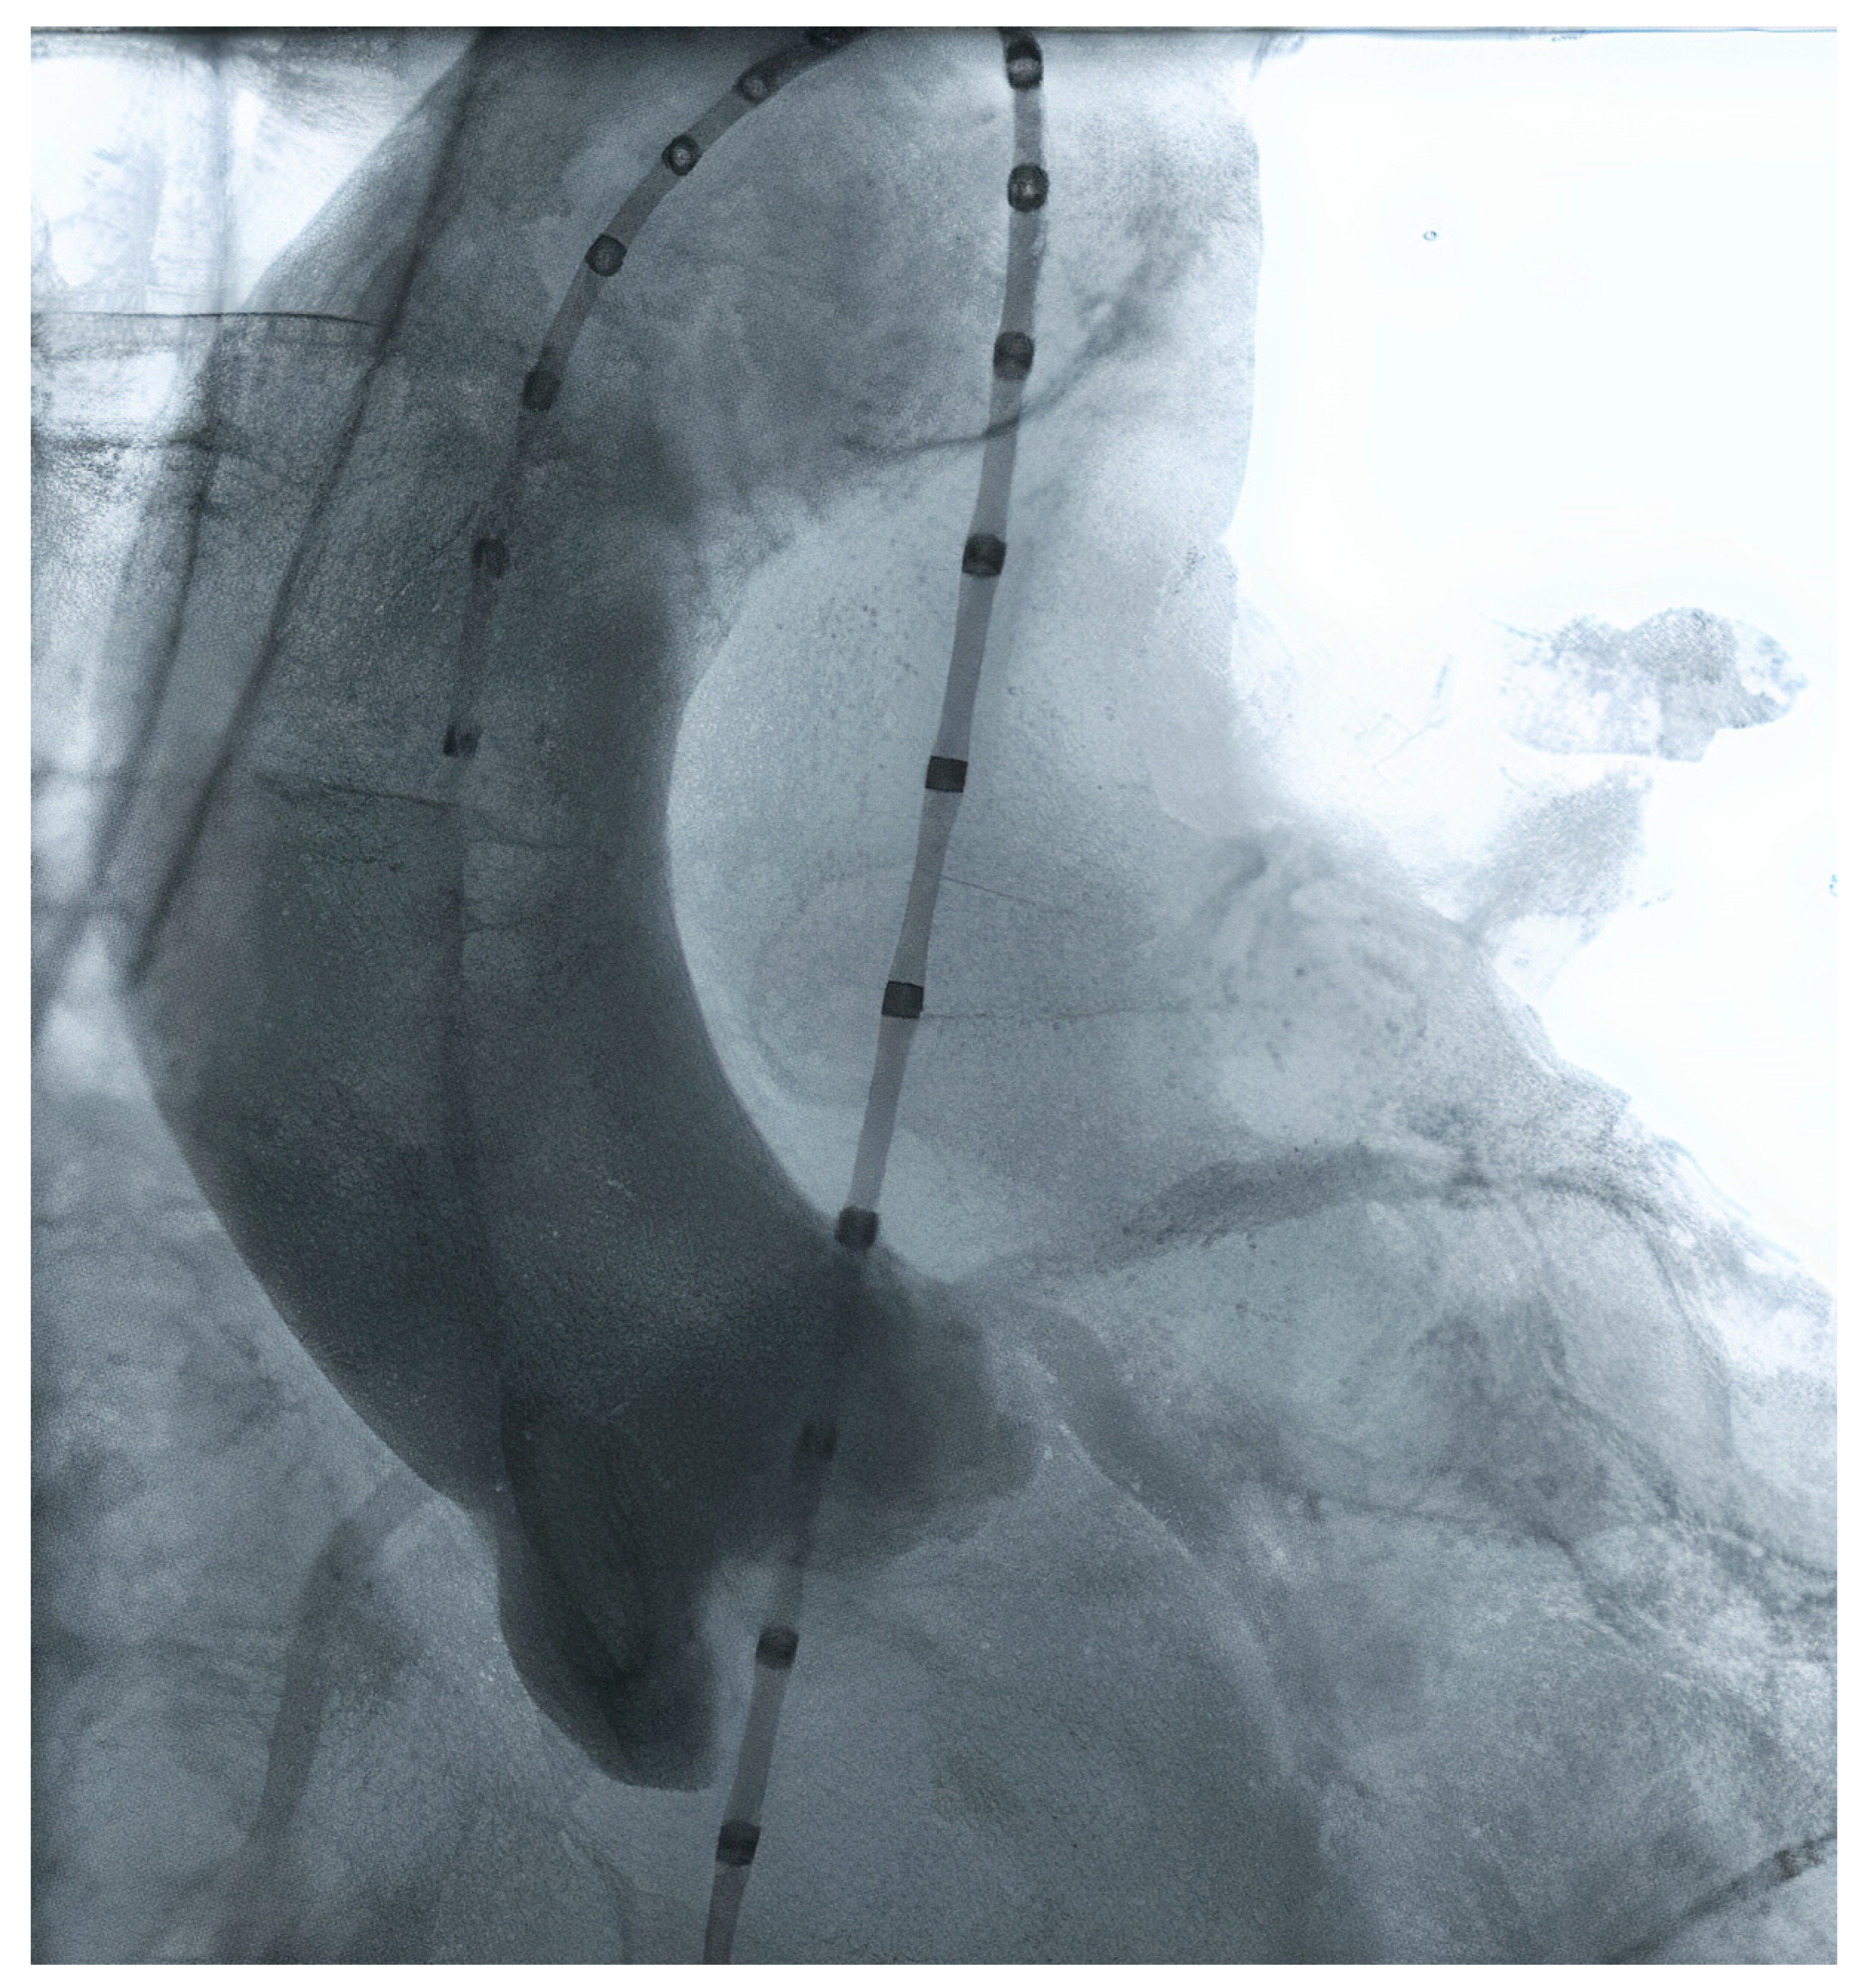

2.7. Peripheral Access Vessels

3.2. Available Methods

3.2.1. Manual Sizing